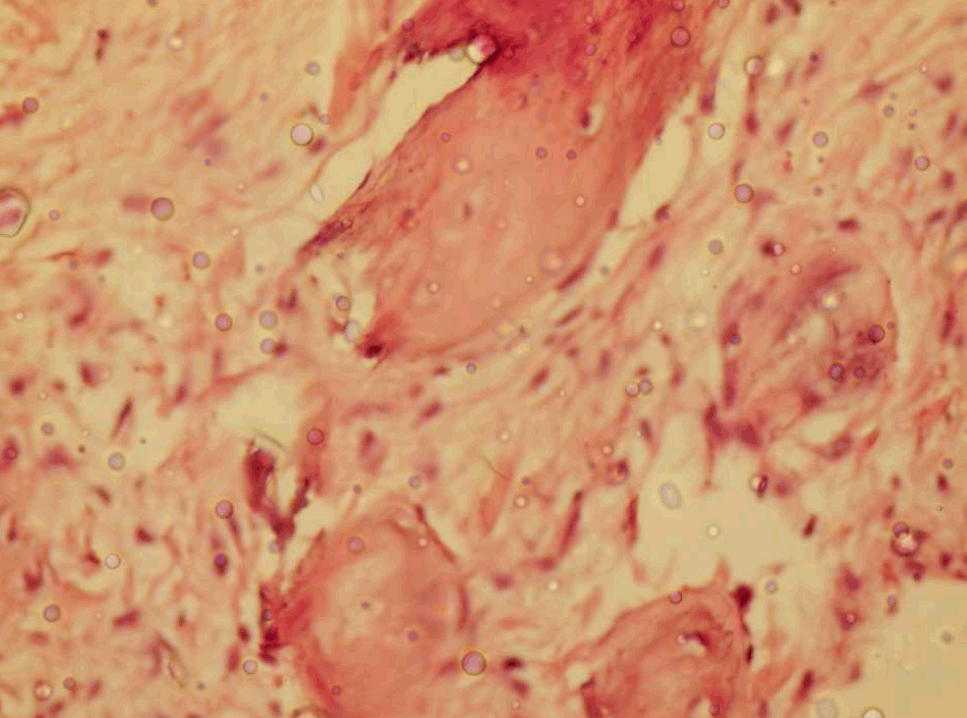

A 25-year-old male patient reported to the outpatient department with a slow-growing painless growth that had been present labially in the left incisor-canine region. The lesion started as a small nodule approximately three years earlier. Examination revealed an approximately 1 cm × 1 cm pedunculated, non-tender, firm, pinkish red growth present on the labial gingiva in relation to the maxillary left central incisor and canine (figure 1). Radiographic examination revealed no significant change in the underlying normal bone architecture The patient's past dental and medical histories were non-contributory. Excisional biopsy was performed. The differential diagnosis included traumatic fibroma and pyogenic granuloma. H&E stained sections shows parakeratinized stratified squamous epithelium and dense fibrous connective tissue stroma. The connective tissue showed dense bundles of collagen fibres (figure 2). Deep in the connective tissue were seen numerous ossifications in the form of bony trabeculae (figure 3). The fibroblasts were plump and active around ossifications.

Figure 3: Photomicrograph showing bony trabeculae surrounded by plump fibroblast (H&E, x400).